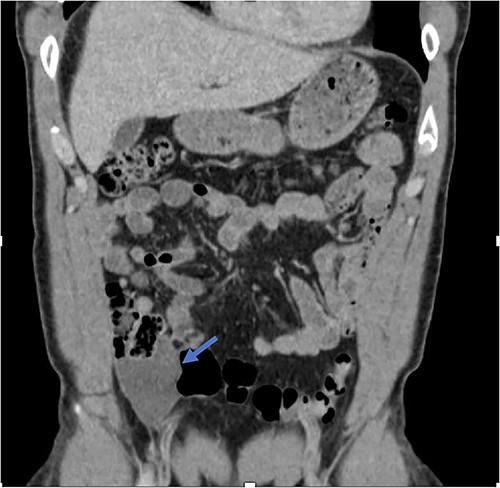

An exploratory laparotomy with a midline incision was performed. Upon inspection of the abdominal cavity, there was no evidence of metastatic disease to the peritoneum, omentum, or liver. A perforated mucinous mass with mucinous collection was identified in the right lower quadrant by the appendix with an additional mucinous collection in the pelvis. Given the appendiceal and cecal involvement, the decision was made to perform a right hemicolectomy and primary anastomosis. Given that this was favored to be a malignant process intraoperatively, the decision was made to perform a right hemicolectomy over a limited ileocolic resection. Lymph nodes were also included due to the extent of the surgical resection. The specimens were sent to pathology. The abdomen was further inspected and subsequently closed (Figs 3–5). The patient tolerated the procedure well, was extubated in the operating room, and recovered in the post-anesthesia care unit in stable condition. The patient was observed postoperatively and was discharged home on postoperative Day 8. The duration of follow-up is 4 months without clinical concerns during follow-up. The final pathology of the specimens revealed LAMN with perforation and associated calcifications. The proximal and distal resection margins were free of neoplasia, and 42 lymph nodes were negative for tumor. There was presence of acellular mucin in the tissue sample, suggesting a favorable prognosis according to previous studies demonstrating that 96% of patients with acellular extra-appendiceal mucin were disease-free at 52 months [5]. Follow-up via surveillance magnetic resonance imaging (MRI) every 6 months, and colonoscopy were recommended. The patient was referred for blood testing, including the tumor marker carcinoembryonic antigen (CEA), which has been unremarkable.

Perforated mucinous mass at the base of the appendix (blue arrow) and mucin collection at the region of the appendix (yellow arrow).